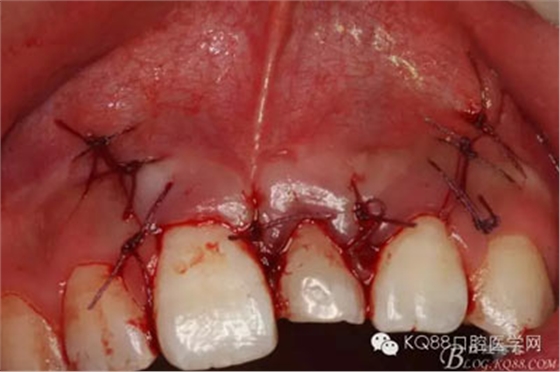

圖18.縫合

圖19.摘除的牙瘤和囊壁組織